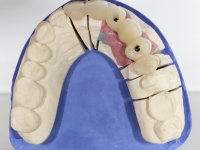

The patient was proposed to undergo a fixed oral rehabilitation consisting of a 2-element bridge over teeth 11 and 21 and a 5-element bridge over 3 implants that would be placed in the location of teeth 22, 24 and 26. The prosthetic structures would have an infrastructure in Zr coated with ceramic and the bridge over the implants would be screwed. The indicated extraction of teeth 25 and 26 and placement of an implant in the 26 site would imply surgery to fill the maxillary sinus. As the patient showed interest in having fixed temporary rehabilitation during treatment, we divided the treatment into 6 phases to achieve this goal: 1- Placement of a temporary bridge over teeth 11,21,25 and 26. With tooth extraction 24. 2- Placement of 2 implants in the location of teeth 22 and 24. 3- Placement of a temporary 6-element bridge over teeth 11 and 21 and over the implants. 4- Carrying out surgery to fill the maxillary sinus. 5 – Placement of the implant in the location of tooth 26 and in the area where the filling of the maxillary sinus was made. 6 – Placement of the definitive work.

A temporary acrylic bridge made in the laboratory with 7 elements was made, with teeth 11,21, 25 and 26 as pillars. The old bridge was removed and tooth 24 was extracted. The provisional bridge after relining was cemented in the mouth. Two implants were placed in the teeth 22 and 24 and 3 months after this intervention an impression was made to make a temporary bridge screwed over the implants and cemented to the teeth. The bridge was placed in the mouth and teeth 25 and 26 were extracted. 3 months later, surgery was performed to fill the maxillary sinus and 6 months later the implant was placed in the location of tooth 26. After osseointegration of this implant, the final impression was made for the final work. The bridge over the implants was permanently screwed on and the bridge over the teeth was cemented with resin-reinforced glass ionomer cement.